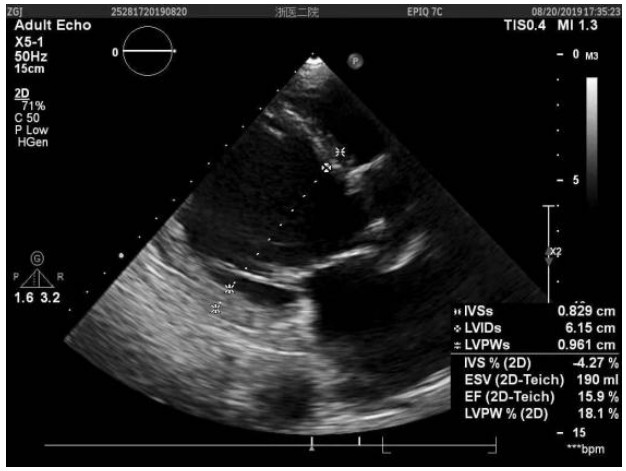

患者行Impella支持期间每日心超提示:左心功能逐步恢复。至辅助第5天时,LVEF达到39%。第9天,血管活性药减停,患者生命指征平稳,心脏基础瓣膜疾病以及ICU机械通气时间较长导致的肺部感染已基本控制。心超示EF约为35%~40%。达到撤机指征,撤除Impella。41 d后,患者于2019年10月18日康复出院,心超(图 2)示LVEF 35.8%,LVEDV 110 mL,LA 3.37 cm。出院后2个月心超(图 3)随访,LVEF 41.1%,LVEDV 85.7 mL。

| 图 3 患者出院后2个月随访心脏超声结果 |